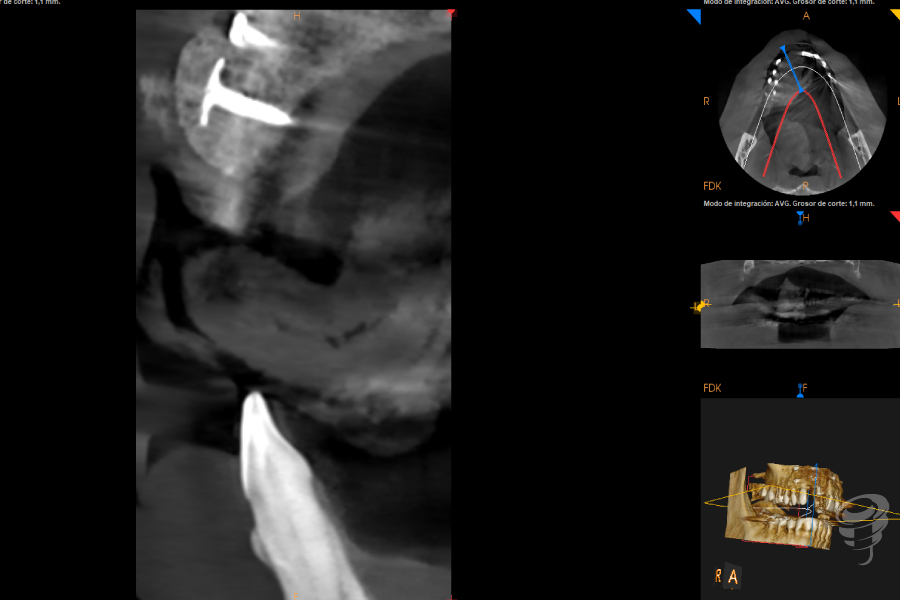

Realizamos un estudio con un CBCT de la zona. En los cortes seccionales se visualiza el implante en una posición muy vestibular, fuera del marco óseo y una imagen radiolúcida rodeando el implante.

Imagen 1

Imagen 2

Imagen 3